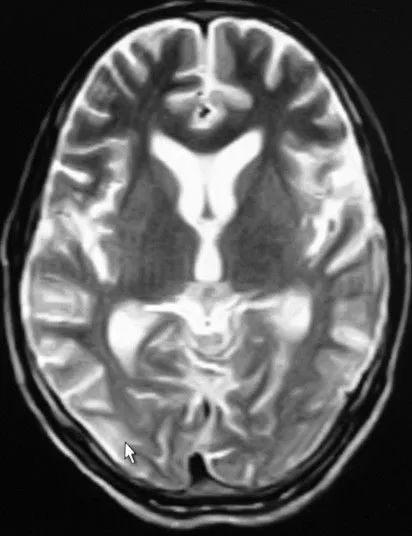

头颅MRI:双侧额颞枕叶可见长T2。

FLAIR呈高信号异常。